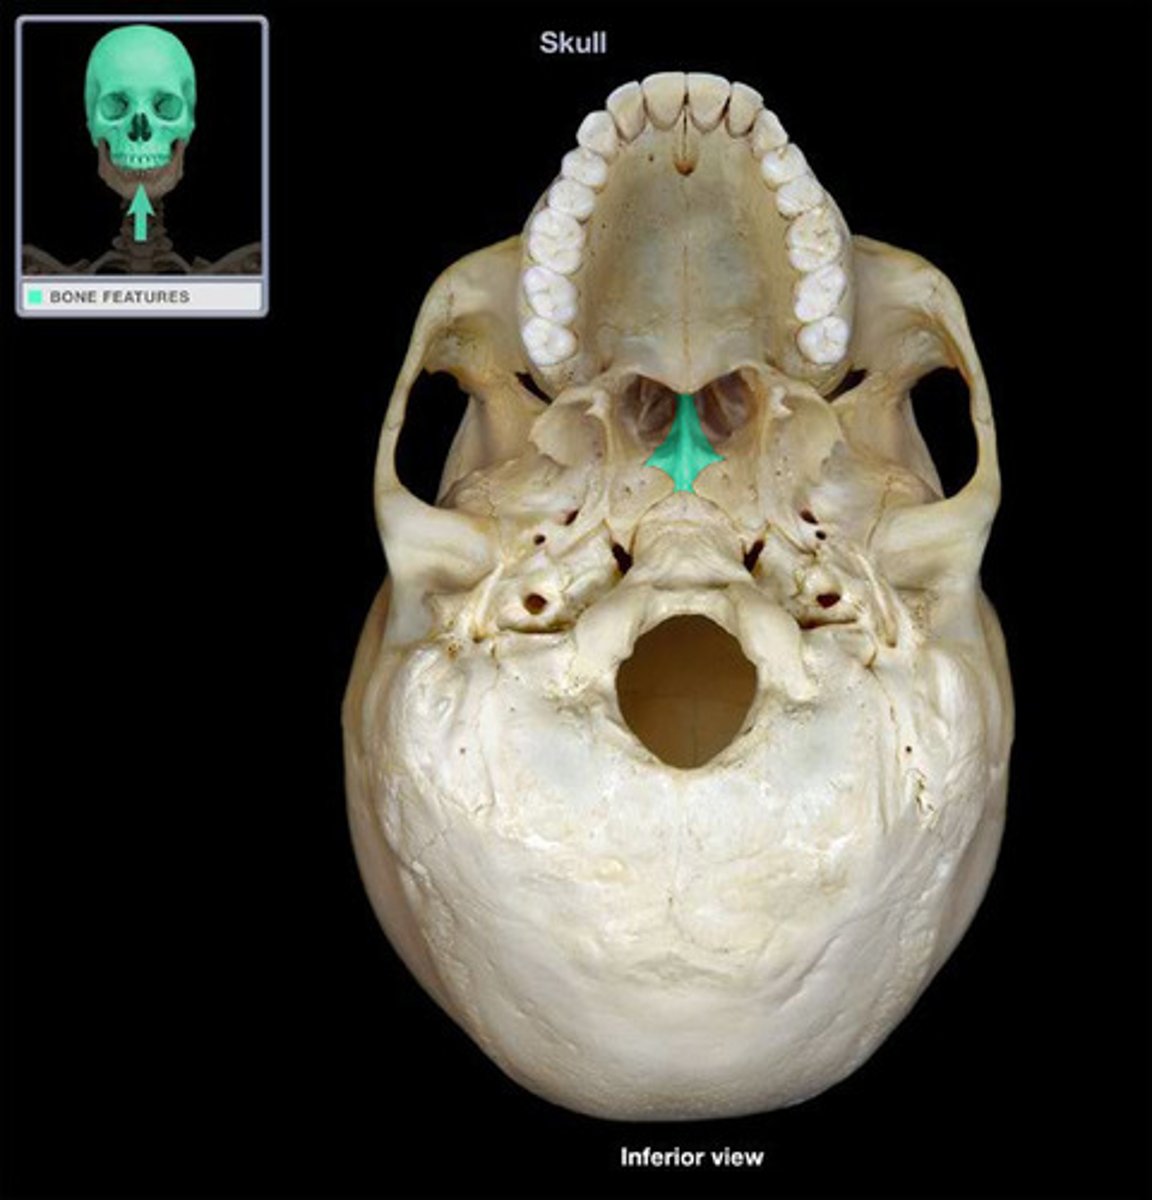

Vomer

Vomer